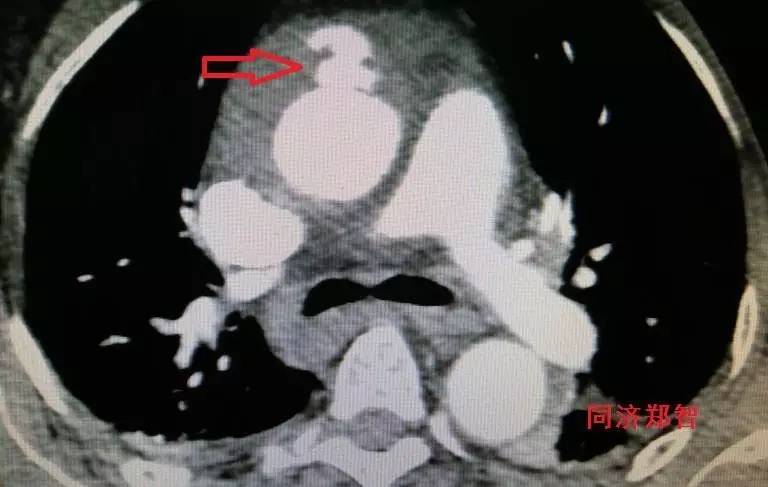

胸降主动脉穿透性溃疡合并壁间血肿(图6),心底层面红箭头所示。

图6